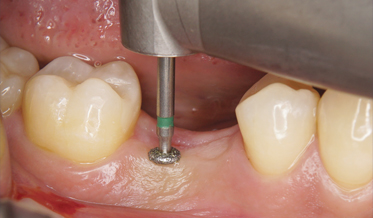

Advances in Esthetic, Immediate Tooth Replacement Therapy Aimed at Improving Clinical Outcomes

Immediate Implant Placement, Immediate Load With Same-Day Fully Digital Fabrication of a Screw-Retained Provisional Implant Prosthesis